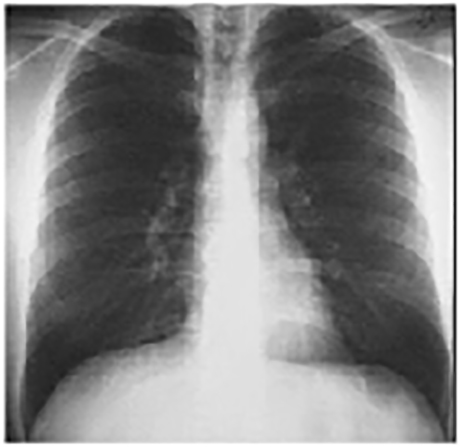

PA view

These chest X rays are normal. The PA view demonstrates no abnormalities of the bone structures, lung fields, or cardiac silhouette. The right and left heart borders are normal as are the great vessels superior to the cardiac silhouette. Note the cardiothoracic ratio is also normal, that is, it is less than 50%. The lateral view is normal, with no evidence of chamber enlargement including the normal anterior shadow of the right ventricle and posteroinferior shadow of the left ventricle.